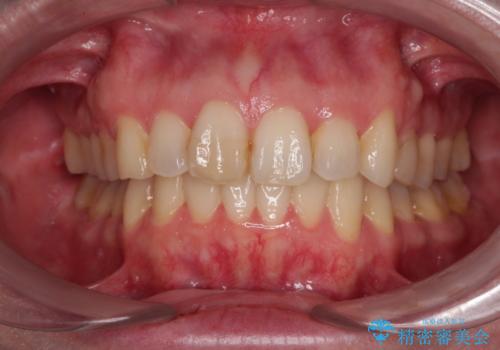

カリエール・ディスタライザーを用いたことで上顎前歯の突出感はスムーズに解消され、歯列不正は1年半ほどでほぼ改善することができました。

しかし、その後インビザライン特有の奥歯がうまく噛めないという問題が長引き、改善に1年近い期間を要することとなりました。